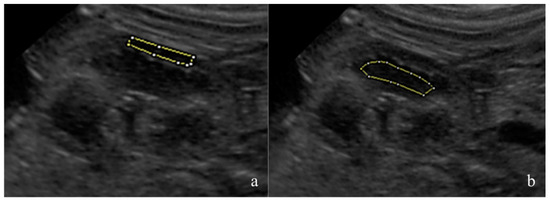

The fetal kidneys of the three most caudal fetuses in both uterine horns were observed and one sonogram of the most superficial kidney was obtained. The renal sonograms were collected using a longitudinal scan, showing the fetal kidney at its maximum length and with an evident cortico-medullary distinction. The renal sonograms were saved in an 8-bit DICOM format and analyzed using dedicated freeware software, Fiji Image J (Image J 1.51h, Java 1.6 0_24 64 bit, National Institute of Health, 9000 Rockville Pike, Bethesda, Maryland 20892 USA). The mean gray level (MGL) and standard deviation (SD) were measured on the manually drawn areas as regions of interest (ROIs). The ROIs were drawn avoiding the renal poles and artifacts [25,26]. For each image, one area was selected in the renal cortex and another in the medullary region (Figure 1). The MGL is the mean echogenicity of the considered area [27], and it was defined as the ratio between the sum of the intensity of the pixels and the number of pixels present in that area. SD is the standard deviation of the intensity of the pixels contained in the ROI, and it estimates the homogeneity of the pixels in the considered area [27]. The cortical MGL (C-MGL), cortical SD (C-SD), medullary MGL (M-MGL) and medullary SD (M-SD) were assessed. The cortical/medullary ratio (C/M) was also calculated using the obtained MGL and SD values.

Figure 1. Ultrasonography representing a normal canine fetal kidney in a longitudinal scan showing its maximal length. The image is stored in an 8-bit DICOM format. A manual outline of the region of interest (ROI) within both the renal cortex (a) and medullary (b) regions were performed by excluding renal poles and any potential artifacts. Subsequently, mean gray level (MGL) and standard deviation (SD) measurements were conducted using Fiji Image J (Image J 1.51h, Java 1.6 0_24 64 bit, National Institute of Health, 9000 Rockville Pike, Bethesda, Maryland 20892 USA).